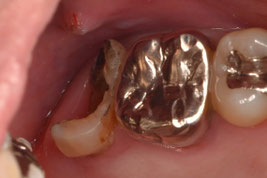

デンタル上で17根尖部から遠心にかけて透過像を認めました。歯冠遠心部はう蝕で崩壊しており、一見すると保存不可能に見える状態です。補綴物を撤去し、軟化象牙質を慎重に除去したところ、近心には十分な健全歯質が残存し、遠心にも健全歯質を保存することができました。レントゲンはあくまで画像であり、実際の状態と相違がある場合があります。レントゲンだけで判断する危険性を、改めて実感しました。

隔壁を作成しラバーダム防湿にて根管治療を施術しました。根管内からは多量の排膿を認めました。初回では可能な限り根管内から排膿させ、水酸化カルシウム製剤を貼薬して仮封しました。仮封すると圧力が高まり、疼痛の原因となりますが、再感染を防ぐために排膿を認めた場合であっても仮封します。ただし、強い疼痛が発現した場合は開放します。